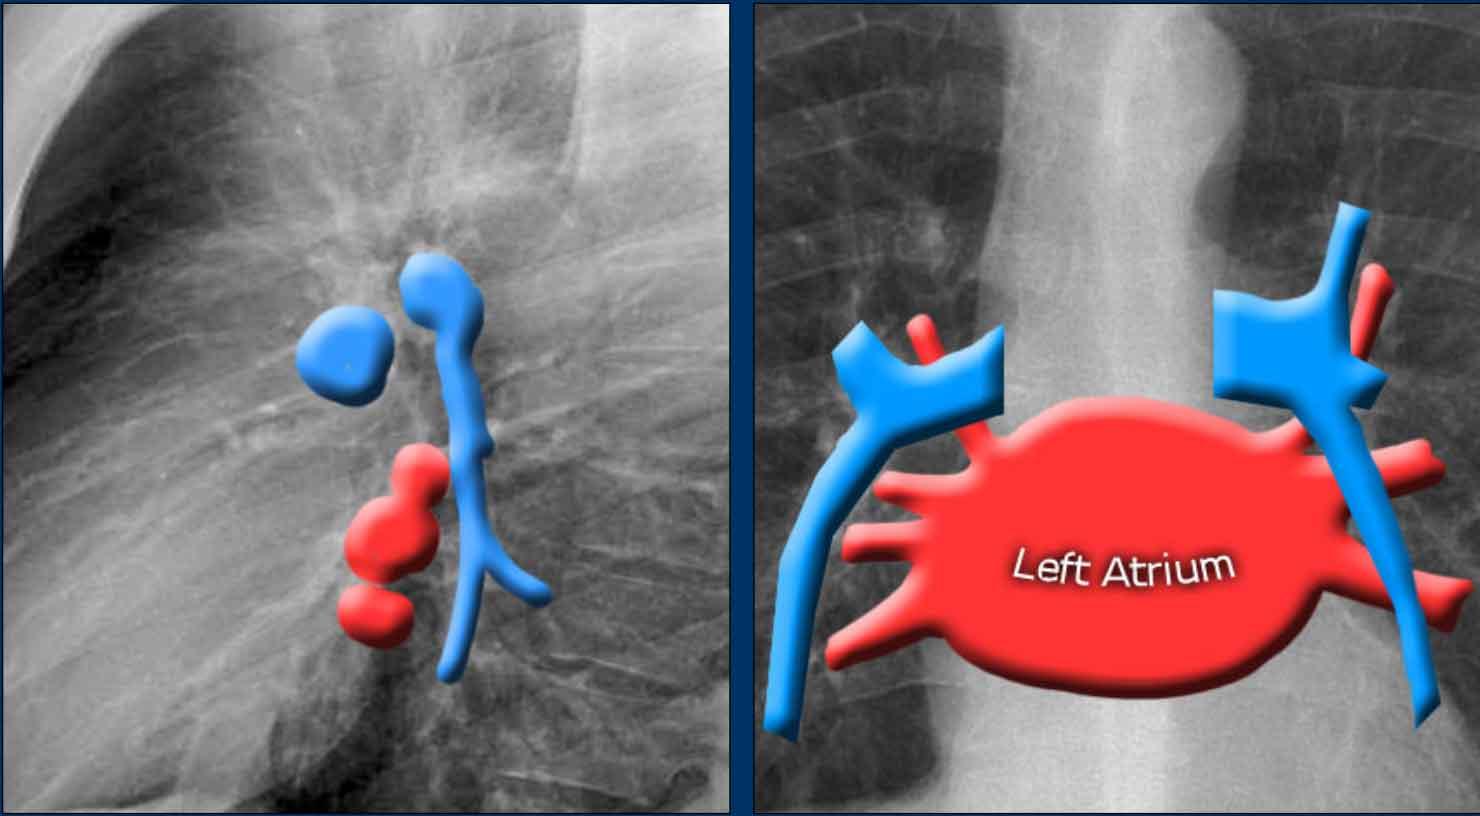

Nhĩ Trái (NT)

Đây là buồng tim nằm sau nhất, nhận máu đã được oxy hóa từ các tĩnh mạch phổi đổ vào nhĩ trái theo hướng gần như nằm ngang. Tiểu nhĩ trái đôi khi có thể nhìn thấy như một phần lồi nhỏ ngay bên dưới thân động mạch phổi (thấy rõ nhất trên tư thế nghiêng).

Dấu hiệu X-quang của giãn nhĩ trái:

- Tư thế thẳng (PA): Phồng bờ tim phải phía trên và mở rộng góc carina do hai phế quản gốc bị đẩy ra hai bên.

- Tư thế nghiêng: Phồng bờ tim sau-trên.

Bờ Từng Buồng Tim trên Tư Thế Nghiêng

- Nhĩ Trái: Tạo thành bờ tim sau-trên; giãn gây phồng ra phía sau.

- Thất Trái: Tạo thành bờ tim sau-dưới; giãn gây di lệch ra sau-dưới.

- Thất Phải: Chiếm khoang sau xương ức phía dưới; giãn lấp đầy khoang sáng sau xương ức theo hướng từ dưới lên trên.

Giãn Nhĩ Trái

- Bệnh nhân có tiền sử bệnh van hai lá mạn tính và thay van tim.

- Giãn nhĩ trái mức độ nặng dẫn đến phồng cả bờ tim phải phía trên (mũi tên đen) và bờ tim sau trên tư thế nghiêng (mũi tên xanh dương).